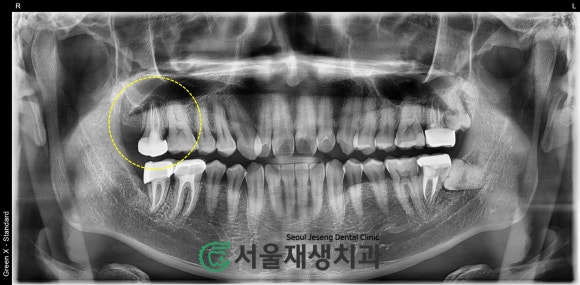

어떤 치아가 원인일까요?

환자분께서는 오른쪽 위 어금니라고

말씀하셨습니다.

정확히 어떤 치아인지 엑스레이를

찍어서 확인해볼게요.

사진상으로 왼쪽 끝 (실제로는 우측)에

환자분이 말씀하신대로 신경치료 된 치아가 있습니다.

해당 치아를 좀 더 확대하여 촬영해봅니다.